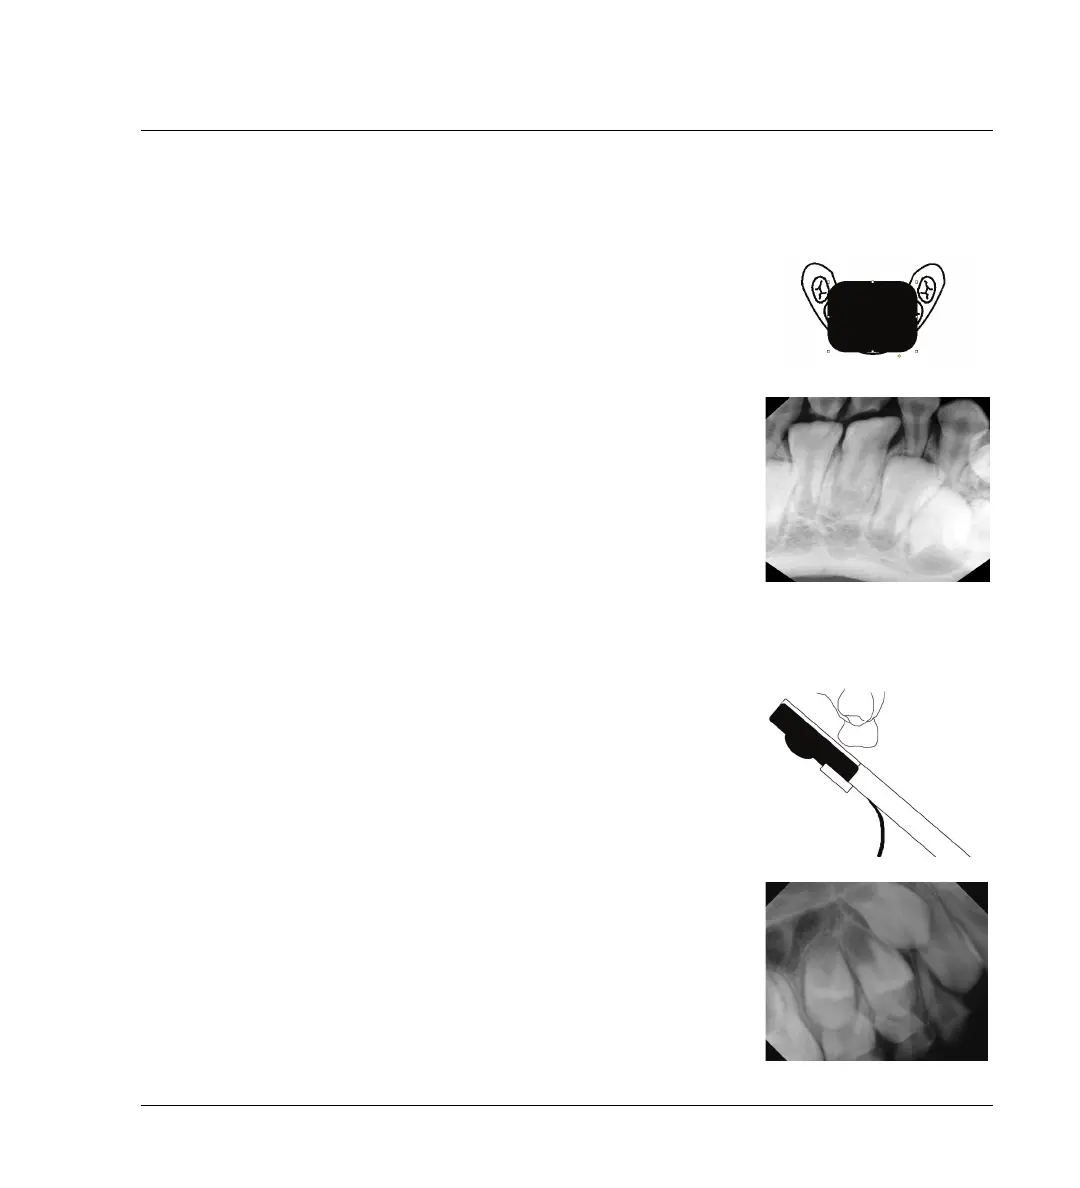

3.4.3 Radiographies occlusales

Vous pouvez à l'occasion avoir besoin d'une vue occlusale.

Image à exposition simple

Pour un jeune enfant, vous pourriez être capable d'utiliser le capteur placé

dans le sens de la longueur de droite à gauche et de capter l'information

nécessaire en une seule exposition.

Technique de bissection d'angle

Placez le support contre le palais et utilisez la technique de bissection

d'angle standard.